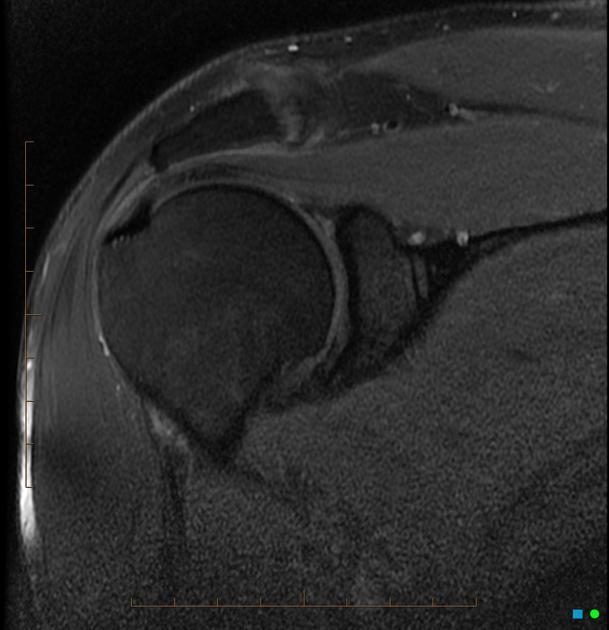

Diagnosis?

Rheumatoid arthritis.